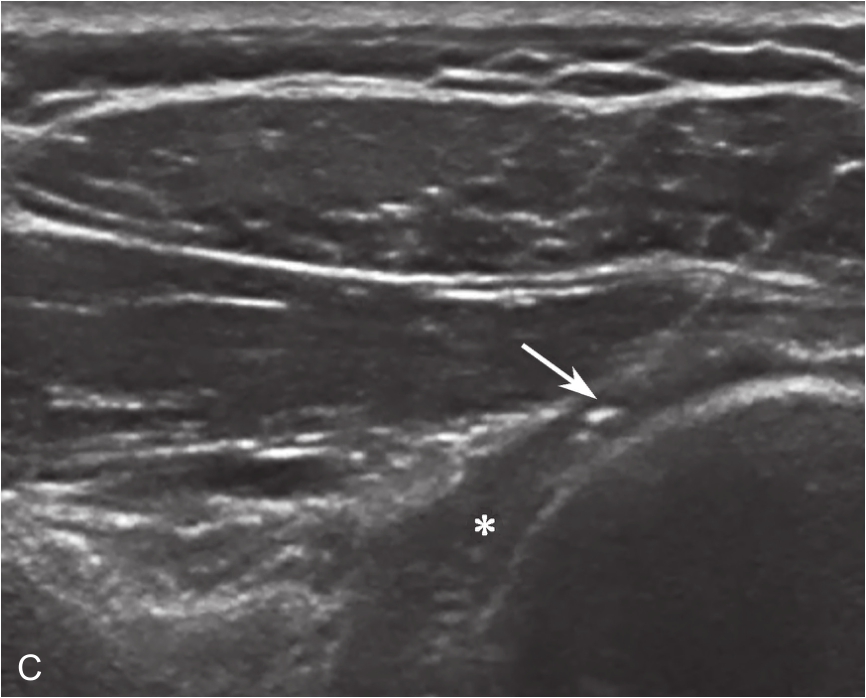

▲ 图2-6-6 超声引导下肩关节腔介入治疗超声图(四)

A.超声引导下穿刺针进入盂肱关节;B.注射治疗后扩张的关节腔;C.注射治疗后关节腔内粘连带;单星号:关节腔;三星号:关节腔内粘连带;箭头:穿刺针